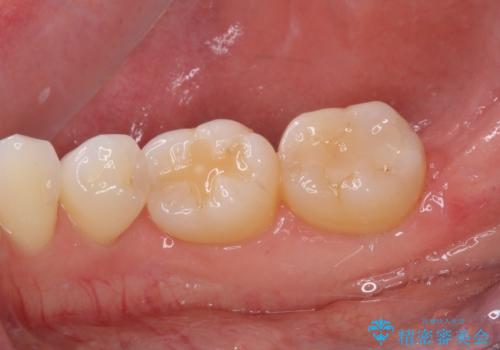

- 上下前歯のデコボコと奥歯の欠損を気にして来院された患者様です。

右下の欠損分は奥歯が倒れ込んでスペースがなくなっていたため、矯正治療により本来の位置に歯を移動させ、オールセラミックブリッジによる欠損補綴治療を行うこととしました。

右下は移動量が多いため、十分な移動が達成されない場合はワイヤー装置を使用する予定としておりましたが、しっかりとマウスピースを装着してくださったため、前歯とともに十分に歯を動かすことができました。